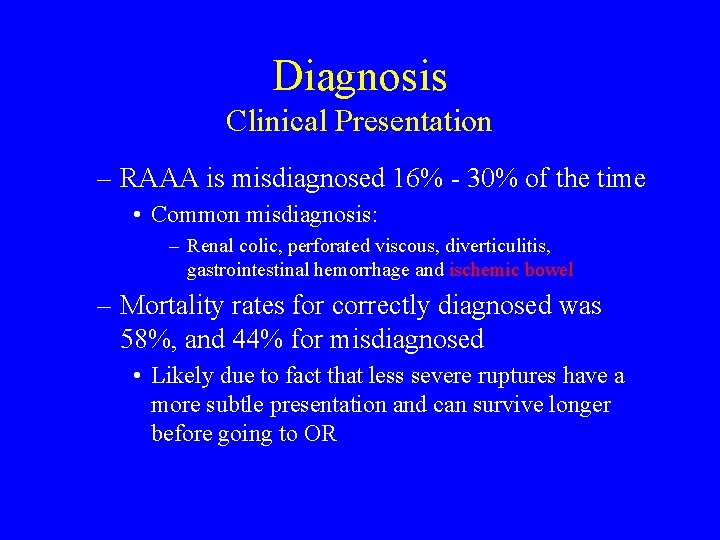

Diagnosis Clinical Presentation – RAAA is misdiagnosed 16% - 30% of the time • Common misdiagnosis: – Renal colic, perforated viscous, diverticulitis, gastrointestinal hemorrhage and ischemic bowel – Mortality rates for correctly diagnosed was 58%, and 44% for misdiagnosed • Likely due to fact that less severe ruptures have a more subtle presentation and can survive longer before going to OR